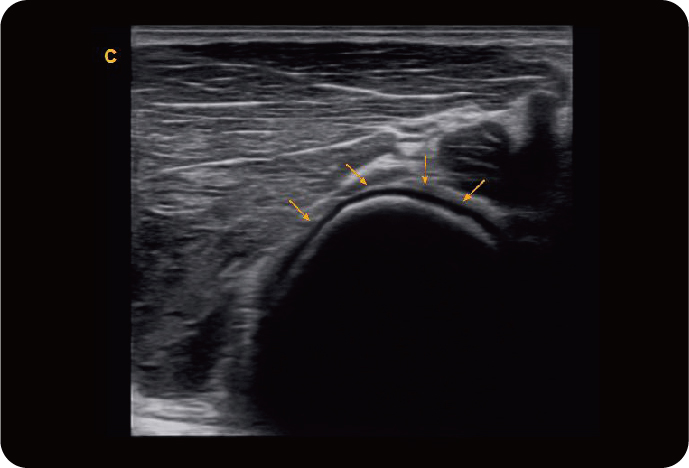

Линейный